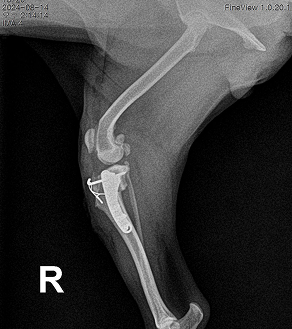

AFTER

완전 파열이 확인된 경우에는 수술이 가장 효과적이고 근본적인 치료 방법입니다. 하지만 저희는 단순히 "무조건 수술"을 권하지 않습니다.

우리 아이가 앞으로 더 오래, 더 건강하게 걷고 뛰는 삶을 살 수 있도록 가장 적절한 치료 시점과 방법을 함께 고민하고 제안해드립니다.

수술은 단지 고통을 없애는 것이 아니라, 반려동물의 일상과 자존감을 회복시키는 과정입니다.